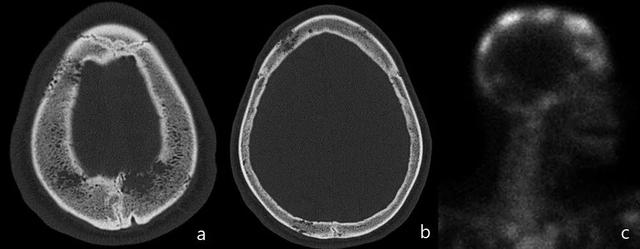

骨髓瘤的一个特征是具有“雨滴颅骨(raindrop skull)”的图案(图7和8)。

图7:骨盆X线片(a):跛行和右侧髋部疼痛的患者,右侧股骨近端明确的溶骨性病变(黄色箭头),皮质破坏。在CT研究(b,c,d和e)中,观察到多个明确边界的皮质下溶骨性病变(红色箭头),提示多发性骨髓瘤。通过骨活检确认诊断。

图8:骨骼调查。多个溶解性病变,具有均匀大小的斑驳图案,颅骨可以观察到“雨滴颅骨”样改变。